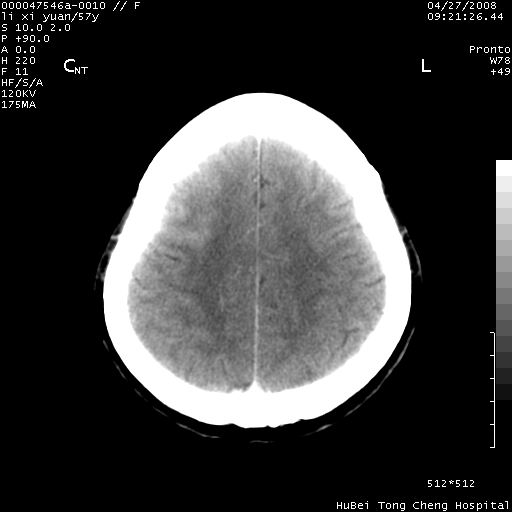

以下是引用余辉在2008-4-27 14:02:00的发言:[br]病灶位于中央沟前方?位于额叶?高密度灶,灶周水肿不明显,病灶似沿脑沟走行,强化明显,局部层面呈现环状强化,考虑1脑表面血管性疾病,如血管瘤,血管扩张,灶内血栓形成,其次考虑肿瘤如脑膜瘤、转移瘤,胶母等

以下是引用形影不离在2008-4-27 14:13:00的发言:[br]考虑胶质瘤可能性大,不排除慢性炎性肉芽肿。建议mri检查。